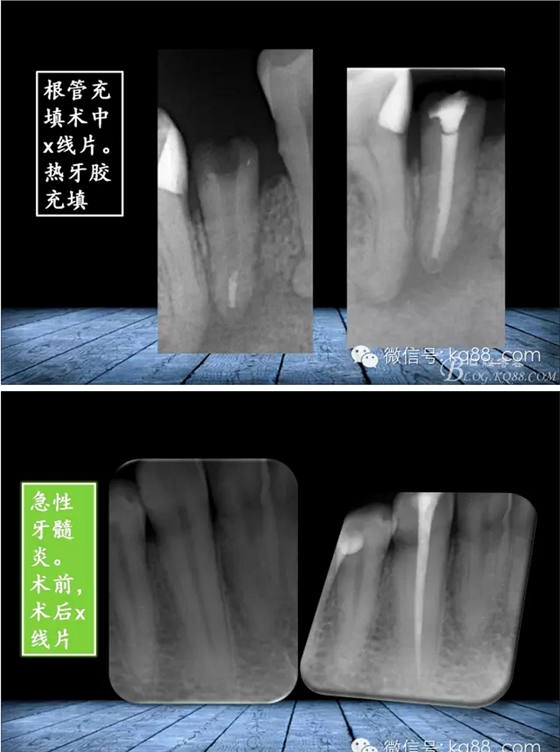

張瑞鋒:簡(jiǎn)單的事情認(rèn)真做——我的根管治療